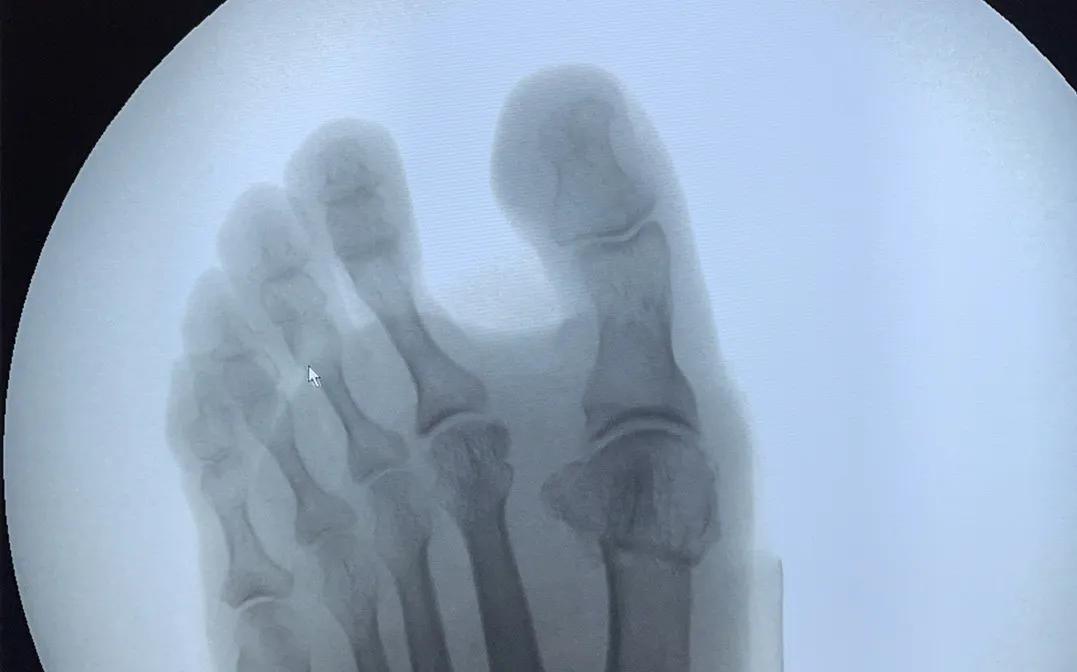

微創(chuàng)矯形助您重拾自信

對(duì)于拇指外翻的干預(yù),通常分為非手術(shù)和手術(shù)兩種方式。對(duì)于非手術(shù)干預(yù)無(wú)效或癥狀嚴(yán)重影響生活的患者,微創(chuàng)矯形手術(shù)是一個(gè)理想的選擇。

>>>微創(chuàng)矯形手術(shù)的優(yōu)勢(shì)

?創(chuàng)口大?。盒g(shù)后創(chuàng)口僅0.5-1cm,疤痕不明顯;

?治療時(shí)長(zhǎng):雙腳手術(shù)僅需30-40分鐘;

?術(shù)后恢復(fù):術(shù)后即可穿戴矯正器,6小時(shí)后可下地行走,6周后可正常穿鞋生活;

?日常生活:微創(chuàng)手術(shù)能有效矯正拇趾外翻,緩解疼痛,改善足部功能。